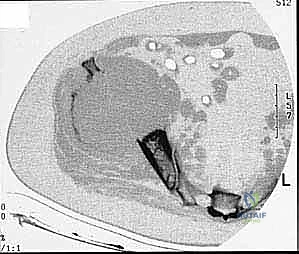

* CT with Intravenous Contrast and 3D Reconstruction (FIG 3): This is our workhorse for assessing bone involvement, destruction, and the critical relationship between the tumor and major pelvic blood vessels. It reveals any distortion of the pelvic anatomy and guides resectability. Figure 3A clearly shows extensive bone destruction and tumor extension into the pelvis and gluteal region. Figure 3C highlights an extensive tumor on the medial aspect of the ilium with destruction of the inner table.

Our patient today presents with a high-grade chondrosarcoma of the left periacetabular region. This is a primary malignant osseous tumor, notorious for its size and myxomatous component, often appearing much larger on advanced imaging than on plain radiographs.